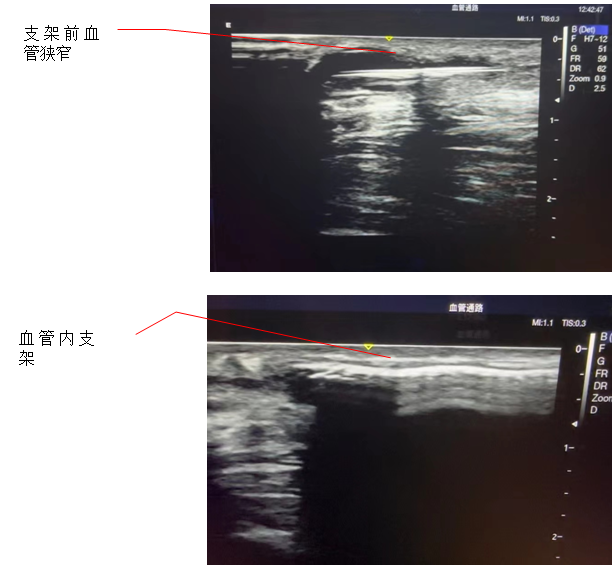

5月24日,黑料网肾病血透中心透析通路团队为一位患者成功实施了人工血管内瘘经皮静脉球囊扩张并覆膜支架植入术,这是黑料网首例在超声下进行的此类手术。

患者为男性,被诊断为慢性肾功能衰竭,使用左前臂人工血管内瘘规律透析1年。患者此前因为人工血管内瘘狭窄曾接受两次经皮静脉球囊扩张术(PTA),但术后狭窄很快复发。内瘘最常见的并发症是狭窄,长期高速的血流会引起血管内膜反应性增生,导致内瘘管腔狭窄和血流量不足。所以,覆膜支架植入术是比较好的解决方法。术后,患者人工血管内瘘血流恢复通畅,透析过程中血流量充足、静脉压正常,达到了较好预期的手术效果。

血液透析通路是尿毒症患者的“生命线”,目前尿毒症患者最常用的透析通路是自体动静脉内瘘和人工血管内瘘。传统的支架植入术是在DSA造影下进行,而超声引导下介入手术是近几年新兴的技术,超声引导具有方便、无辐射损伤、无造影剂损害、可显示闭塞病变等优点,特别适合动静脉内瘘等外周血管的介入治疗。